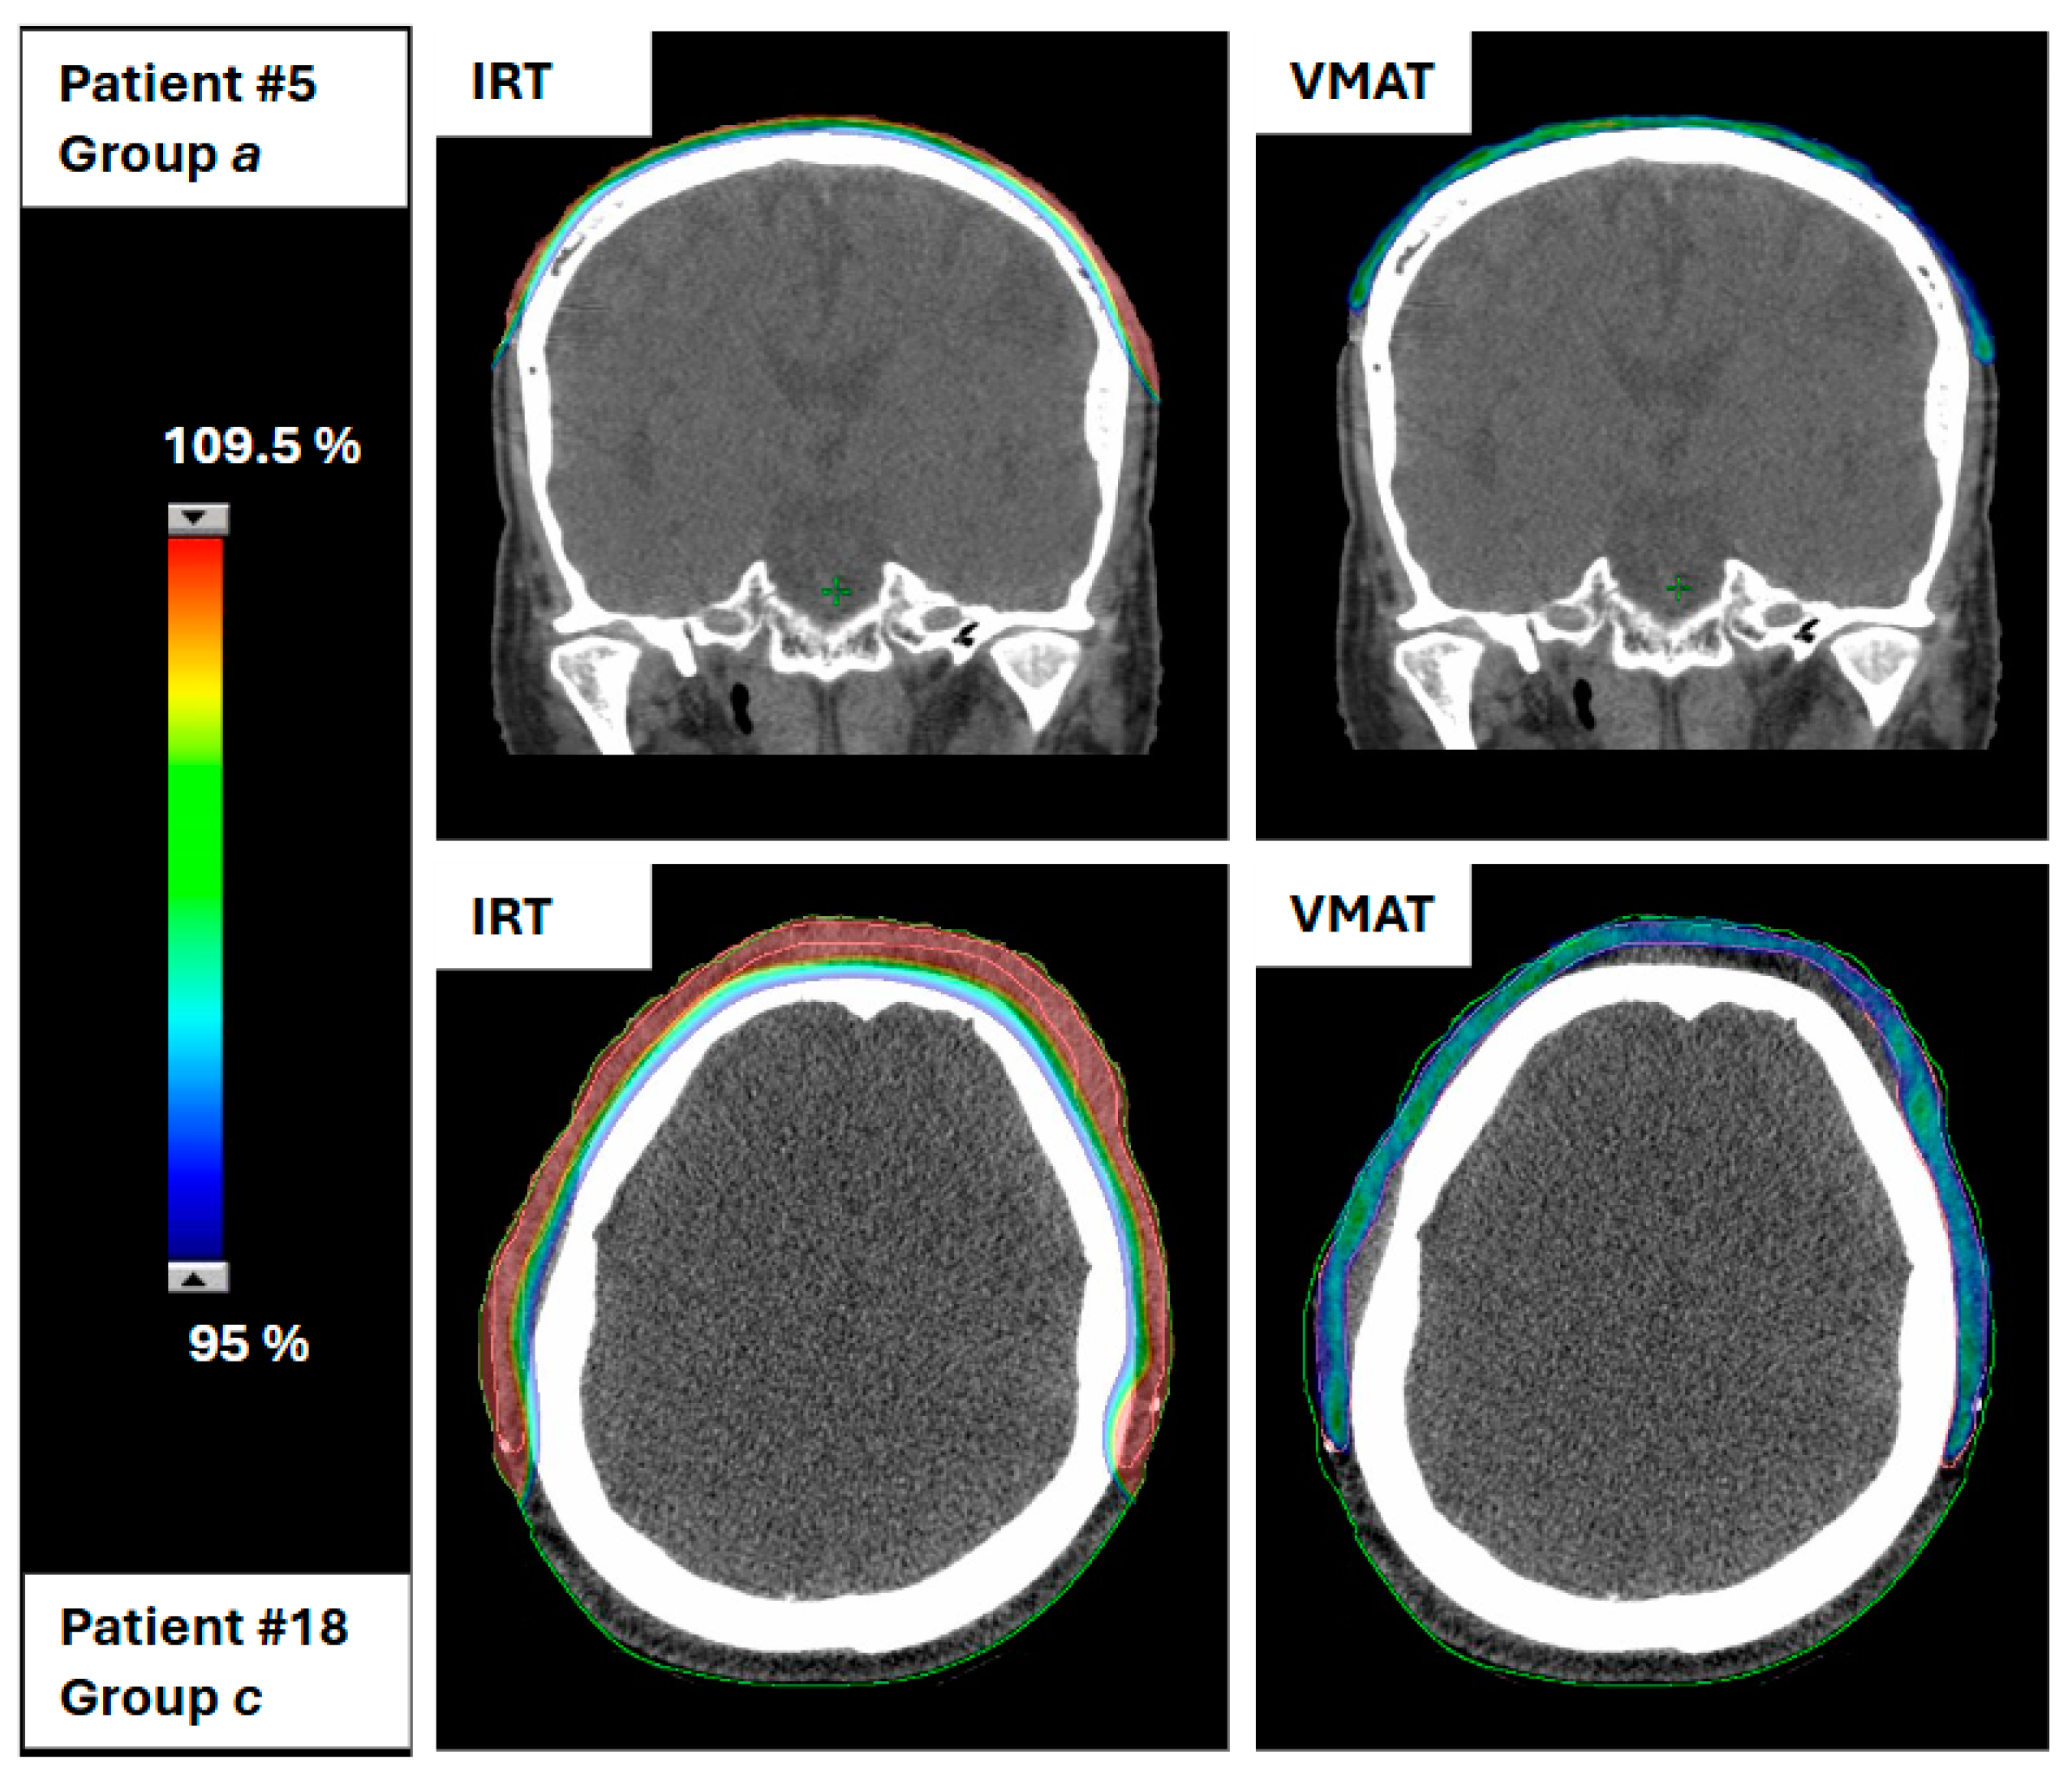

Of the 25 patients included in the study, 2 (specifically, 1 from group A and 1 from group C) could not have an electron beam therapy plan created because it was not feasible due to the extensive size of the clinical target volume (CTV). In particular, patient 18 had a CTV volume of 142.2 cc, and patient 5 had a CTV volume of 75.1 cc, making electron therapy impractical for these cases. Figure 1 shows the 95% dose coverage of the CTV for the IRT and VMAT treatment plans for these two patients.

Figure 1. A 95% dose coverage of the CTV for the IRT and VMAT plans for two patients where the electron plan was not feasible due to the extensive CTV volume.